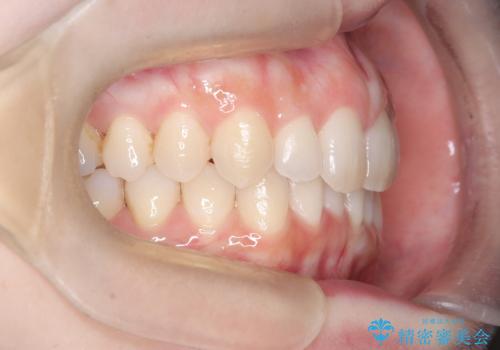

インビザラインで整えた前歯の歯並び

- 患者様は、上下前歯の歯列不正(ガタガタ)を主訴としてご来院されました。治療計画として、透明なマウスピース型矯正装置「インビザライン」を使用し、約2年の期間を見込んで前歯部の歯列を整える方針を立てました。特に下顎前歯に歯肉退縮のリスクがあるため、治療中にIPR(インタープロキシマルリダクション)を行い、歯間を適切に削ることで、過度な圧力を避け、歯肉退縮を防ぎながら配列を進めました。治療は慎重に進め、最終的にきれいで整った前歯の歯並びを目指しました。

インビザラインによる矯正治療は、患者様自身が装着するマウスピース型の装置を使用するため、装着時間の徹底が重要です。特に、下顎前歯の歯肉退縮を避けるため、IPRを施すことで歯間スペースを確保し、歯肉にかかる負担を減らしました。この方法により、歯並びを整えながらも歯肉の健康を保つことができます。治療期間中は定期的にチェックを行い、歯肉の状態や歯の動きを慎重に確認しました。また、治療後はリテーナーを装着して歯並びを維持し、安定させました。